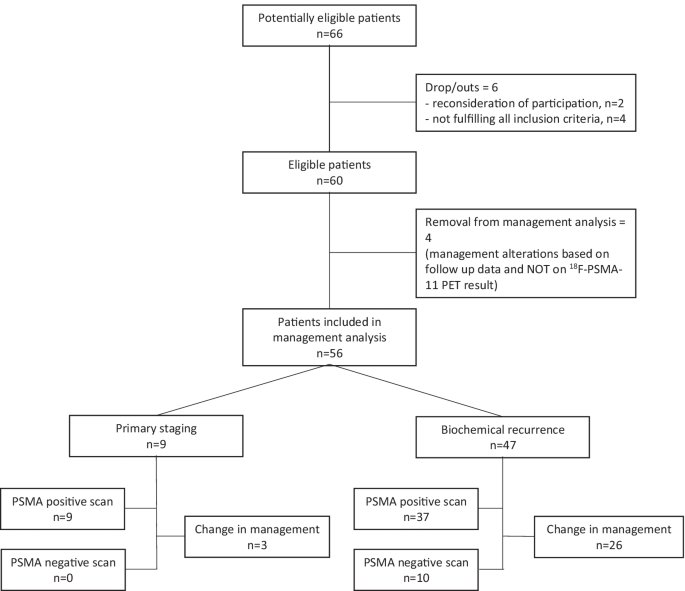

Impact of 18F-PSMA-11 PET/CT on Management of Biochemical